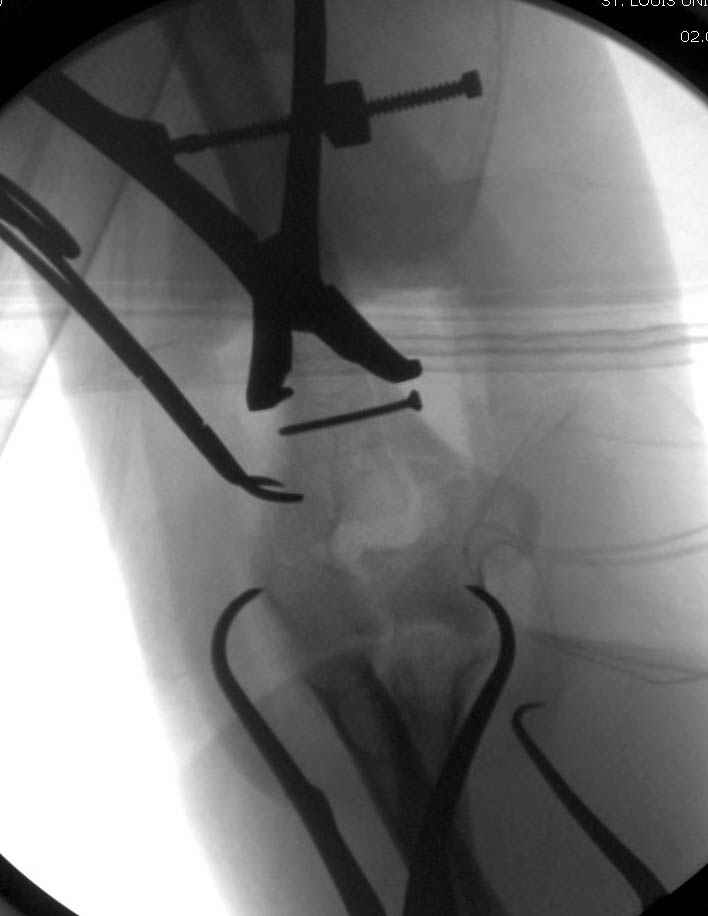

Больному сделали обработку и наложили временный аппарат внешной фиксации плечо-предплечье.

На шестой день сделали открытую репозицию чрезлоктевым доступом двумя locking plate, локтевой нерв был ушибленным, после операции положительная динамика в Flexor Carpi Ulnaris. Фиксацию локтевого отростка произвели tension band technique с дополнительным шурупом.

Этапы операции на снимках....